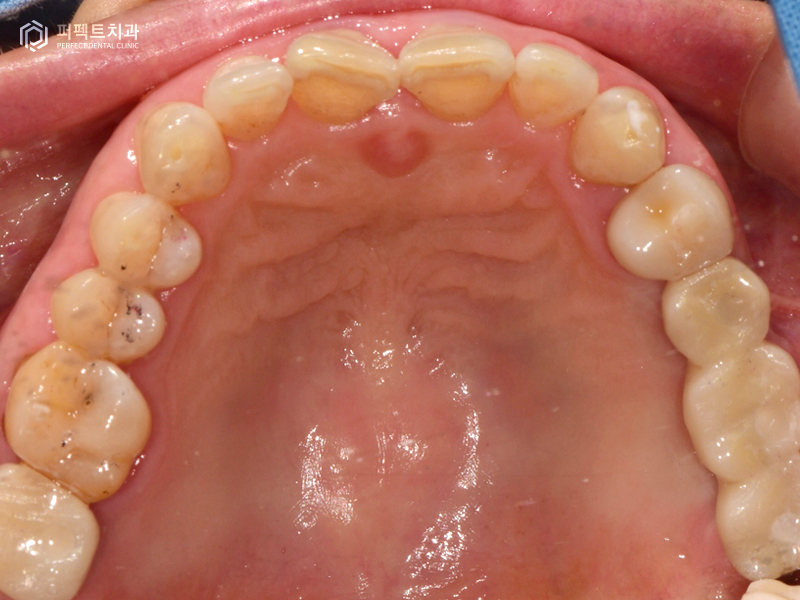

3번의 내원으로 임플란트 식립을 모두 마치게 되었고, 5~6개월이 지나고 임플란트와 뼈가 다 붙은 후에 다시 내원해주셨습니다. 본원에서는 구강을 스캔하여 3d로 만드는 작업을 하고 있는데, 이 작업을 통해 당일에 보철 6개를 끼워 마무리 하였습니다.

환자분의 경우 총 임플란트 6개, 지르코니아 크라운 1개의 치료를 받으셨는데 총 5번의 내원으로 해결을 할 수 있었습니다.